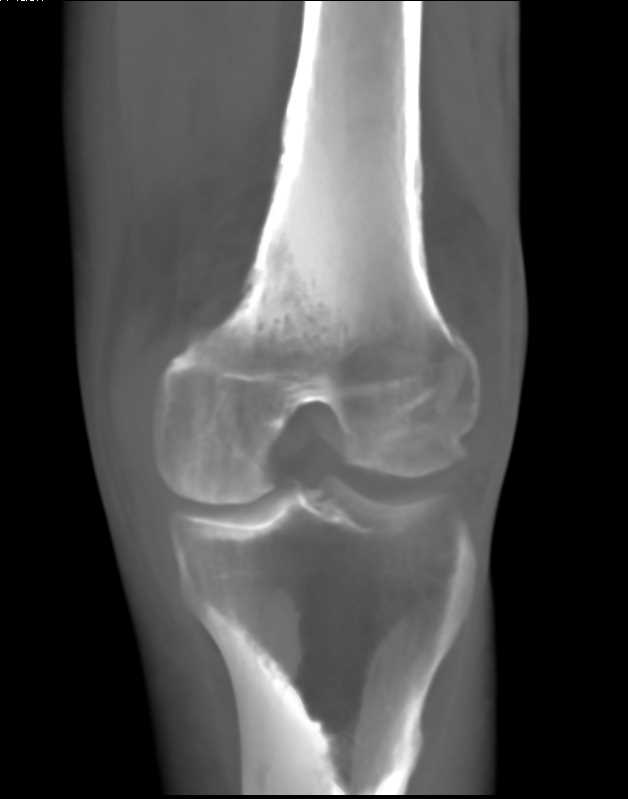

Femur and Tibial Fractures